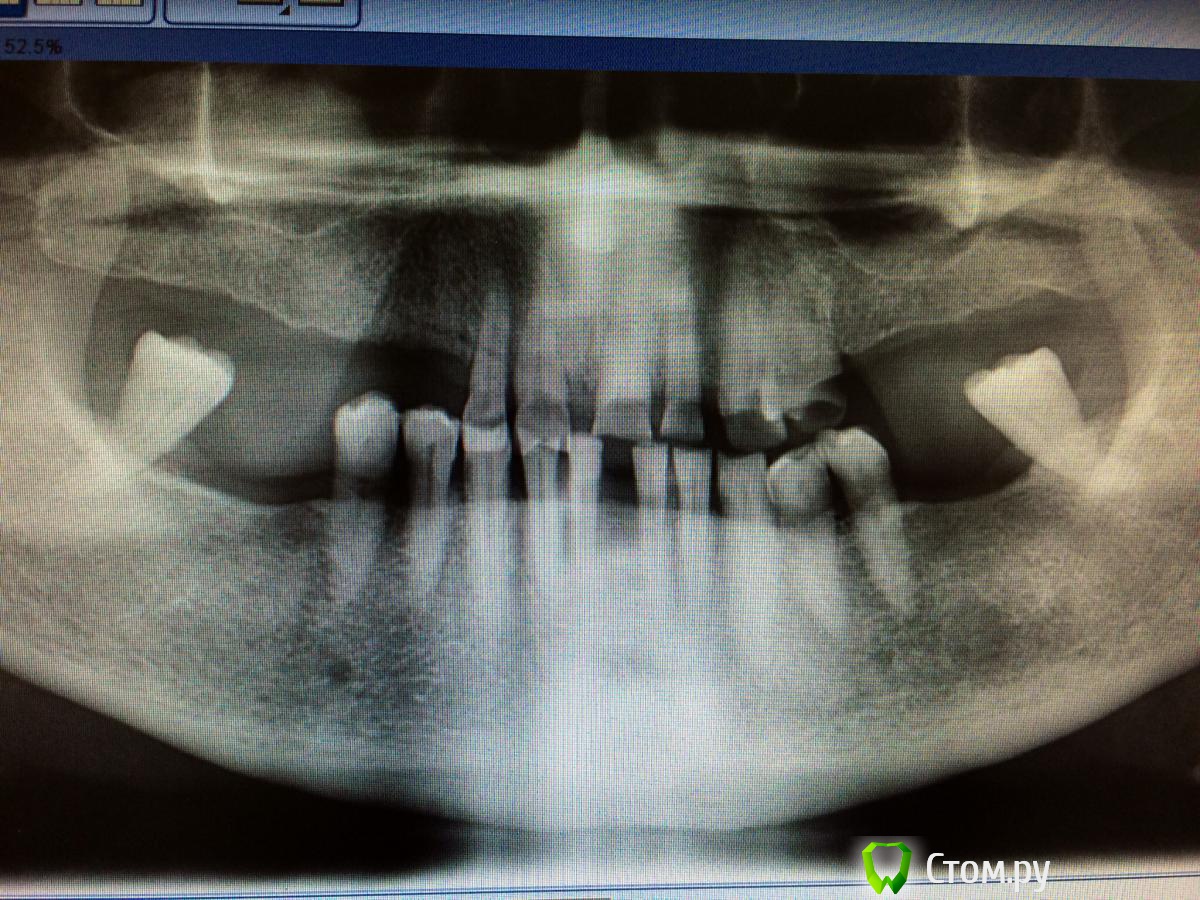

Jenechkin Опубликовано 7 октября, 2014 Поделиться Опубликовано 7 октября, 2014 Уважаемые коллеги! Вопрос по составлению плана лечения - планируется съемное протезирование. Как быть с нижними молярами и центральными нижними резцами, удалять или все таки можно мостовидные конструкции сделать...? Спасибо! Ссылка на комментарий

DR.P Опубликовано 7 октября, 2014 Поделиться Опубликовано 7 октября, 2014 Если не рассматривать имплантацию:Я бы не стал на н.Ч. тянуть мосты на моляры при такой атрофии точно. Будет жевать и вывихнет и со временем - мк мост даст трещину. Тут на нч, считаю, лучше удалять моляры, делать мост на фронт и бюгель на замках или телескопах с опорой на (3.4,3.5,4.4,4.5)Что касаемо верха, почти все зубы ВКВ и тоже либы МК мост + ЧСПП или бюгель на телескопахКто не согласен - поправьте. Ссылка на комментарий

LuckyDoc Опубликовано 8 октября, 2014 Поделиться Опубликовано 8 октября, 2014 Нижние резцы выполнить с закрытием промежутков не удастся, слишком широко, если нет подвижности, для эстетики одиночки с тремами, либо мост со сверхкомплектным резцом,в акурат получится по средней линии) судя по фото прогеническое соотношение? При состоянии ОФП, сколько мм сагитальная щель? Ссылка на комментарий

DR.P Опубликовано 11 октября, 2014 Поделиться Опубликовано 11 октября, 2014 мое мнение, моляры низ точно на выход. Обосную: атрофия кости на 2/3 и более, а корни сходящиеся в один апекс. Они долго не прослужат. Все-таки лучше связать все зубы на н.ч. и бюгель на замках 1 Ссылка на комментарий

chervoncevdaniil Опубликовано 12 октября, 2014 Поделиться Опубликовано 12 октября, 2014 мое мнение, моляры низ точно на выход. Обосную: атрофия кости на 2/3 и более, а корни сходящиеся в один апекс. Они долго не прослужат. Все-таки лучше связать все зубы на н.ч. и бюгель на замкахА какая атрофия кости допустима,чтобы оставить зуб,например,под опору моста или под опору кламмера?если бы был такой же зуб,но на половину в кости,оставили бы?вопрос ко всем Ссылка на комментарий

DR.P Опубликовано 12 октября, 2014 Поделиться Опубликовано 12 октября, 2014 Я уважаю одонтопародонтограмму Курляндского: очень просто можно высчитать коэффициенты с учетом атрофии и зубов антагонистов - все индивидуально Ссылка на комментарий